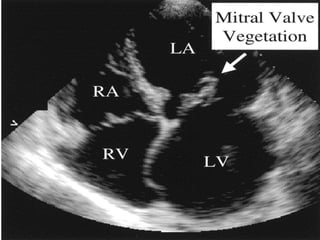

ECHOCARDIOGRAPHY

 Major duke criteria

 Vegetations-detectes in 67% of “definite” cases by

duke criteria

 -Irregular shape

 -Occur on low pressure side of turbulent jet

 *Atrial side in mitral and Tricuspid regurgitation

 *Ventricular side in aortic and pulmonic

regurgitation

 May occur on other nonvalvular locations

Sachdeva,187-188

Typical echo features

 Oscillating intracardiac mass on a valve or

supporting structure or device or in the path of a

regurgitant stream

 Abscess

 New partial dehiscence of prosthetic valve

 New valvular regurgitation